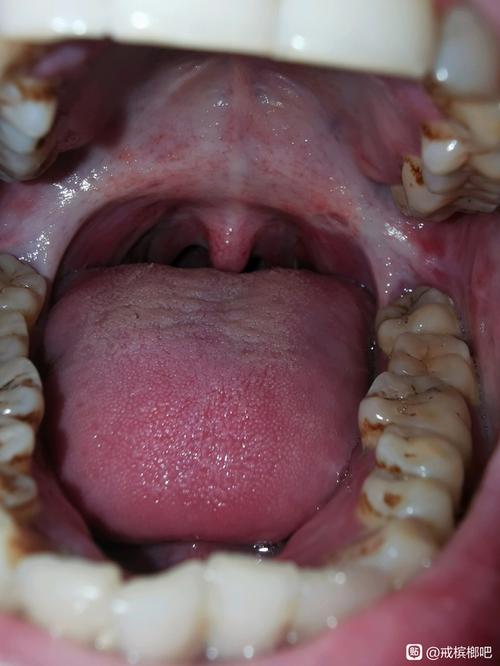

口腔黏膜下纤维化是一种慢性、隐匿性、具有癌变风险的疾病,其本质是口腔黏膜和深层结缔组织因慢性刺激(主要是咀嚼槟榔)而发生的胶原纤维过度增生与变性,导致组织失去弹性、变硬,最终引起张口受限和吞咽困难。

晚期意味着疾病已经发展到非常严重的阶段,组织结构和功能都受到了不可逆的损害。

晚期的主要临床表现

晚期的症状会非常显著和痛苦,严重影响患者的生活质量。

张口受限 - 最典型的晚期症状

- 原因: 口腔软组织(包括颊黏膜、唇、舌系带、软腭等)因纤维化而变得像皮革一样坚硬、缺乏弹性,纤维组织挛缩,像“瘢痕”一样将上下颌骨“拉”在一起。

- 表现:

- 患者可能只能张开手指宽度(1-3厘米)的口,甚至完全无法张口。

- 无法正常进食、刷牙、说话,甚至呼吸困难。

- 张口时伴随剧烈疼痛和牵拉感。

- 临床检查: 详细询问病史(特别是槟榔咀嚼史),评估张口度(用手指测量)、检查黏膜颜色、质地、弹性以及有无癌变迹象。